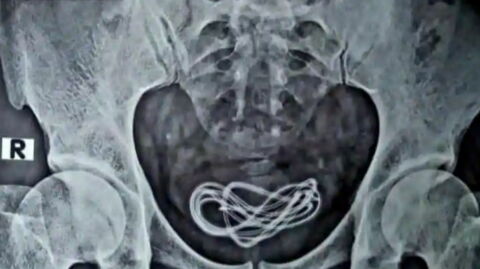

When the patient, who had been suffering from depression for 30 years, was examined after arriving at the medical centre in the Japanese capital, doctors observed that his abdomen was tense and painful. They sent him to the radiographer to find out what was causing this peritoneal discomfort and they found that his thorax and stomach were full of strange, round objects.

The man went in for emergency surgery which revealed that there were 1894 coins inside his stomach. On the plus side, he beat the previous record for the number of coins removed from a body, 600 to be more precise, which were removed from an American in 2008.

The Japanese patient apparently didn’t care about the coinsbefore swallowing them, since 1, 5, 10, 50 and 100 yen coins were all removed from his stomach. This anatomic coin purse, that contained an equivalent of around £120, had nonetheless caused a puncture in his gastric wall. But the man was lucky enough not to contract zinc poisoning, seeing as though zinc is a metal that is generally found in coins. As the Réalités biomédicales article explains: